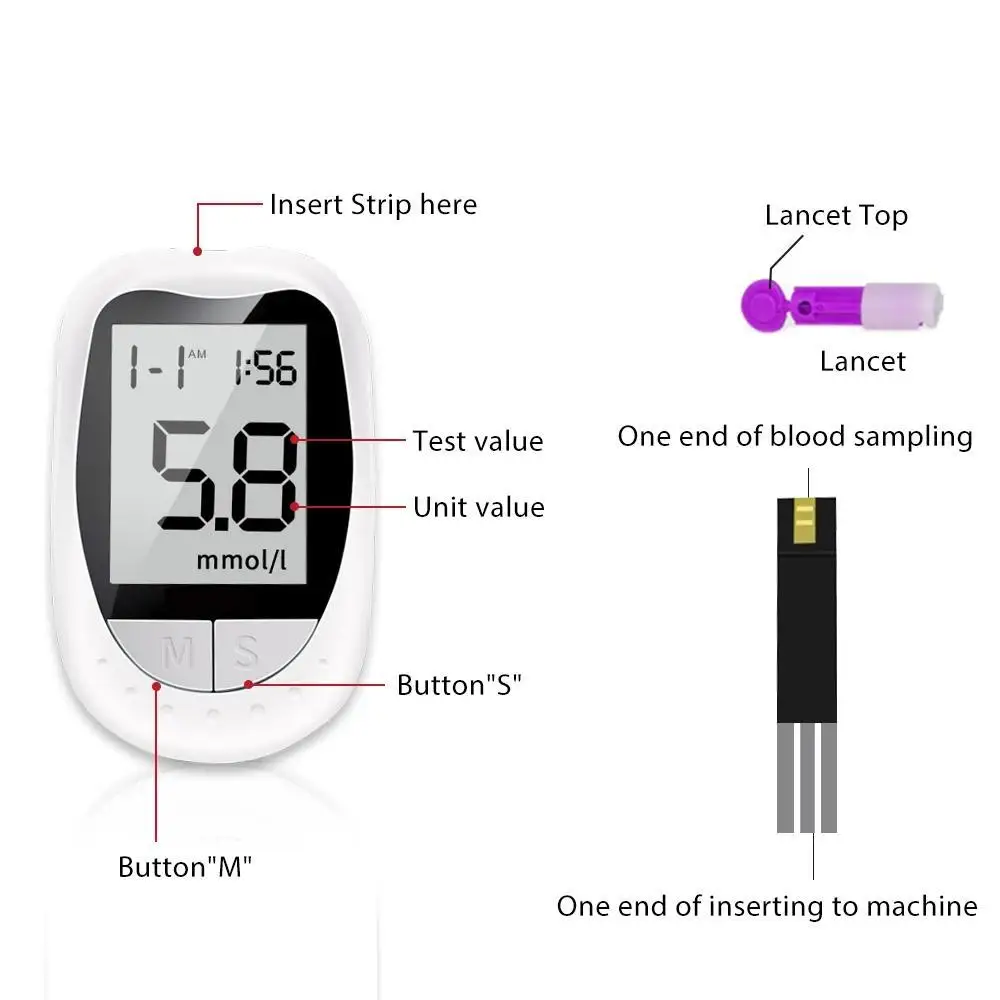

Application: Fingers

Power supply: CR2032 button battery (not included)

Units: mmol/L and mg/dl

Test range: 1.1-33.3 mmol/L (20-600mg/dl)

Test sample: whole blood of capillaries

Minimum volume added: 1ul

Test time: 7s

Battery life: tested approximately 1000 times

Memory value: 200x

HCT range: 30-55%